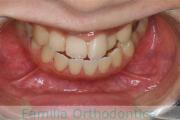

No.20V-496

- 叢生

- 15歳

- 女性

- 上:

- 84|58

- 下:

- 8558

- FEA

- 80万円

全体的なでこぼこを治したいということで来院されました。上顎は右は4,左と下顎両側は5番を抜歯して、マルチブラケット法にて治療を行いました。2年強、25回程度の通院をしていただきました。

非常に強いでこぼこですので、後戻りのリスクは高めであると思われます。